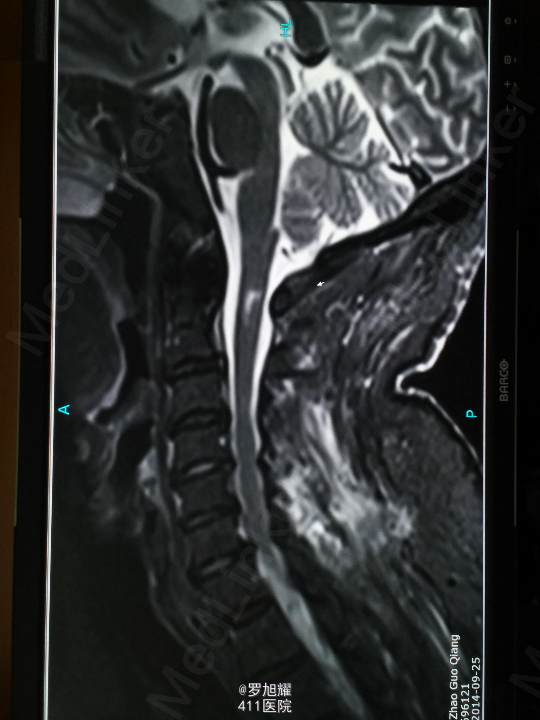

左侧锁骨平面以下痛温觉、位置觉消失,右半身感觉正常。会阴部感觉存在。左侧肢体肌力正常,右侧上下肢肌力0级。右侧腱反射均消失。影像学检查示双侧枢椎椎弓骨折,MRI脂肪抑制成像颈1-2平面脊髓信号略高。

入院立即给与大剂量甲强龙冲击治疗,辅以甘露醇脱水消肿,兰索拉唑保护胃黏膜,腺苷钴胺恩经复营养神经,伤后10天复查MRI脊髓信号增高明显,两周后生命体征稳定,肢体感觉和肌力见部分恢复,行颈2椎弓根螺钉、颈3侧块钉内固定术,因神经压迫不明显未行椎板切除减压。 术后3月骨折线基本消失,患者感觉肌力几乎完全正常,右肩残留疼痛磁共振检查发现肩袖损伤,暂予局封治疗症状缓解。